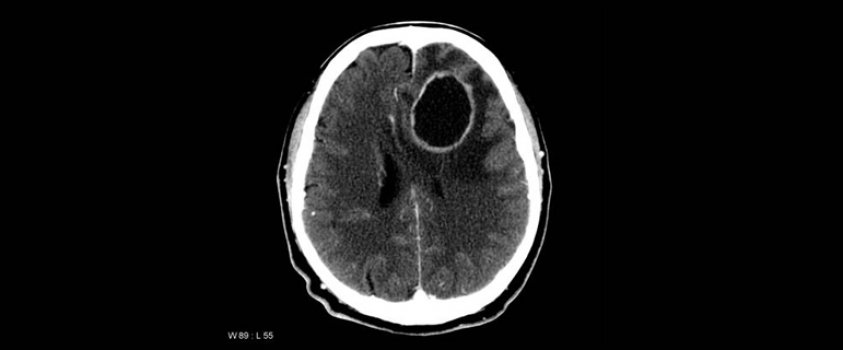

Fenomen je u medicini poznat kao anterogradna amnezija. Za razliku od klasične, retrogradne amnezije, kod koje se pacijent ne sjeća ničega od prije traume koja ju je prouzrokovala, kod anterogradne amnezije to mu se događa doslovno svaki dan: ne može zapamtiti više od nekoliko posljednjih trenutaka, mozak ih nije u stanju iz kratkoročne memorije pohraniti u dugoročnu, pa ih istog časa briše, onemogućavajući stvaranje novih sjećanja. Oboljelom od anterogradne amnezije svako je jutro početak života, svakoga dana on ponovo otkriva sebe, i oko sebe čudesni novi svijet.

Anterogradna amnezija spada u razmjerno neistražene tajne ljudskog mozga. Prvi sustavno dokumentirani slučaj bio je onaj iz 1957., kad se Amerikanac Henry Molaison zbog epilepsije podvrgnuo lobektomiji, pa izgubio sposobnost pamćenja više od nekoliko posljednjih minuta. Još je, međutim, rijeđi i neistraženiji fenomen kolektivne anterogradne amnezije. Najpoznatiji takav, i najbolje dokumentiran, jest slučaj jednog malog europskog naroda, Hrvata, čija historijska memorija traje jedva nekoliko mjeseci.

Kako se to i zašto događa, znanost pouzdano ne zna. Anterogradna amnezija još je, rekoh, neistraženi misterij, pa kako ne zna ni kako točno nastaje, nije medicina načisto ni kako da joj doskoči. U mračnom psihološkom trileru Memento, gledali ste možda, glavni junak jednako ne može zapamtiti više od posljednjih nekoliko minuta, pa rekonstruira svoje sjećanje vodeći bilješke i snimajući svakodnevnicu Polaroidom, čak i tetovirajući važne informacije na vlastito tijelo.